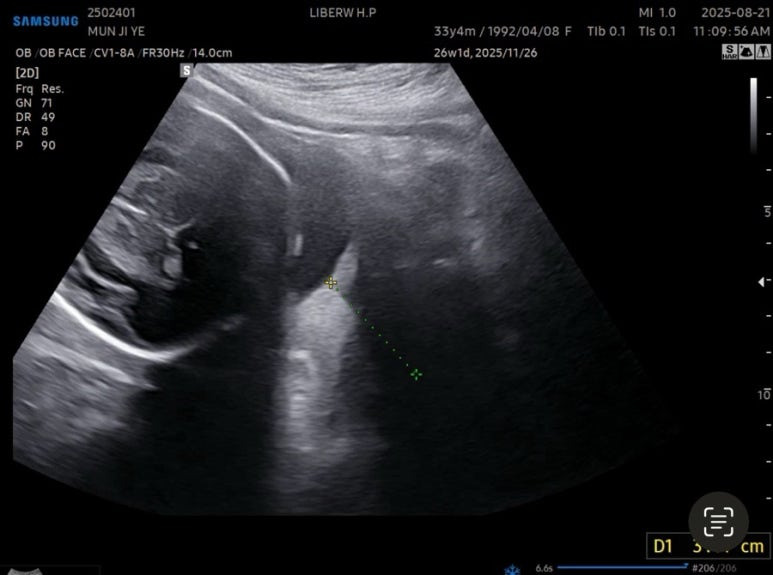

경부길이 3.44cm